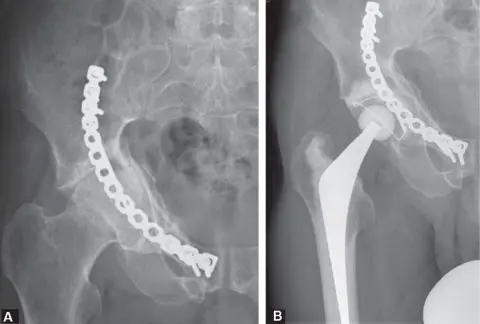

<img alt="وصف طبي دقيق للمريض" class="img-fluid rounded shadow-sm d-block mx-auto my-4" loading="lazy" src="/media/upload/a7dbb80a-49c5-4b41-b295-430553bad3e7.jpg" style="max-height: 600px